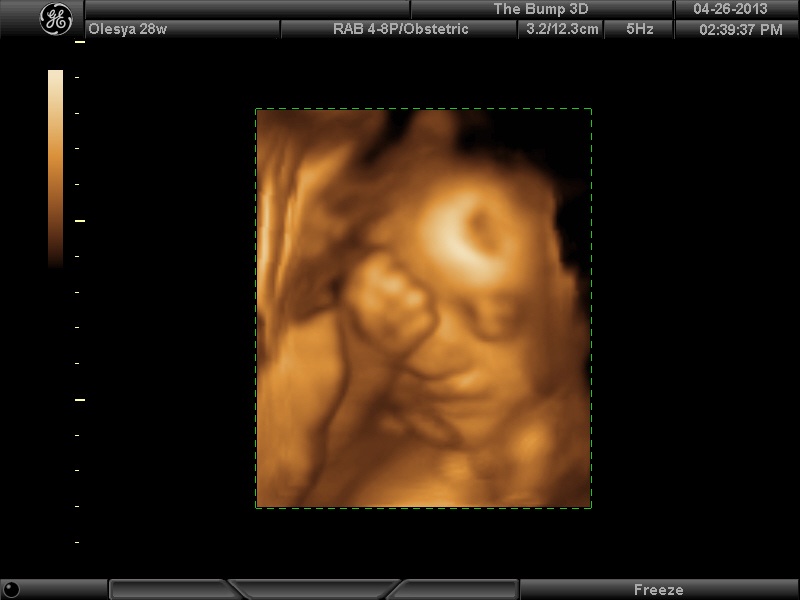

Вот, наш губошлёп:)

| Вложения: |

FACE.png [ 91.95 КБ | Просмотров: 1217 ]

Ой, Ксюнь, класс!!! Я говорю у вас у всех очертания носика, губок видны отлично...у моей же все размыто как-то и везде разное. На одной фотке вообще не нос а аэродром. Я ничего не поняла. Но УЗИстка сказала что она очень близко к плаценте мордашкой была поэтому так мутно все. Я надеюсь они мне переделают бесплатно все же. Я бы очень хотела. Так рассмотреть охото как следует, за это ведь и платила как никак..:-)